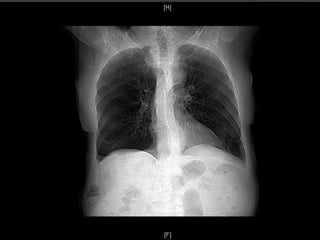

Suites Post-operatoires: CTA

 Aucunes

endofuites ou

migration

 Exclusion

complete et

thrombose de

artere lusorienne

ainsi que le

diverticule

Cas1

 Aucunes complications post-operatoire

 Duree hospitaliere:

 6 jours

 Suite post-opératoire:

 Asymptomatique (resolution de la toux)

 CTA a 4 mois post TEVAR